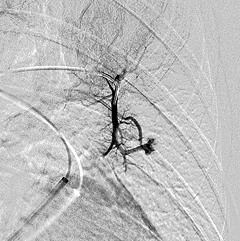

A pulmonary angiogram and embolization is a minimally-invasive procedure performed by an interventional radiologist in an angiography suite. The patient is given sedation for this procedure. A catheter (a small tube) is inserted into an artery in the top of the thigh and directed through the body to the site where the embolization will be performed. An embolization coil is then injected through the catheter to block the blood flow through the AVM. After the procedure, the patient is transferred to the recovery area, where he or she is observed for several hours before being discharged home.

Pulmonary angiogram depicting

Pulmonary Arteriovenous Malformations (PAVMs).